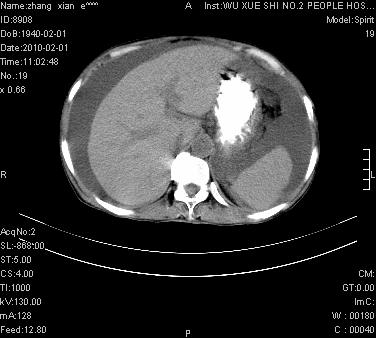

标题: CT24434:70岁 女 腹胀,腹水原因待查 [打印本页]

大量腹水,脾脏囊性占位,子宫颈占位,右侧腹股沟淋巴结肿大,建议+c,先查妇科。

腹盆腔大量积液,子宫增大,子宫颈增大外形不规则,内见低密度影,膀胱后壁显示不清,右腹股沟肿大淋巴结,脾脏囊性占位,子宫颈占位,子宫颈癌?建议增强。

子宫、宫颈占位?转移性腹水?肝性腹水?脾脏囊性占位,囊肿?血管瘤?淋巴瘤?

考虑:1、腹膜转移,大量腹水;2、脾占位性病变;3、左侧卵巢占位性病变,建议增强进一步检查。支持